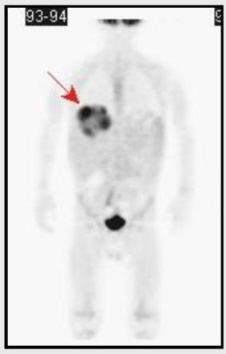

4. pacient

Tříletý chlapec odeslán pro neznámý novotvar v

oblasti retroperitonea. PET/CT prokázal velké ložisko v pravém

jaterním laloku.